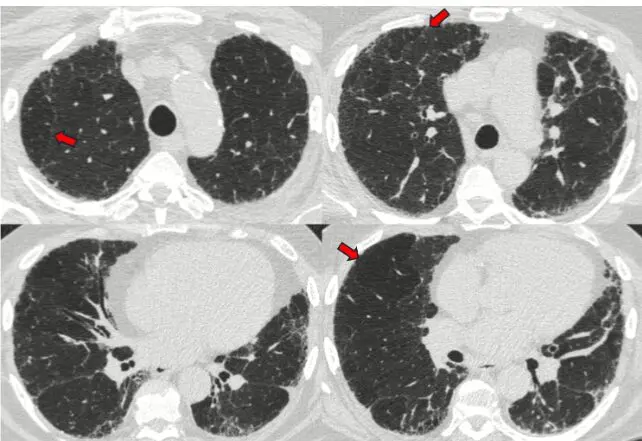

論文のFigure1を引用。この症例は、モザイクパターン(赤色矢印)の存在により、60%の確信度で「alternative」であると判断。しかし、放射線科医は同時に「definite UIP」の可能性も40%あると判断した。

例えば、あるHRCT画像を評価した場合に、

- alternative 60%

- definite UIP 40%

のような評価を許す設計です。